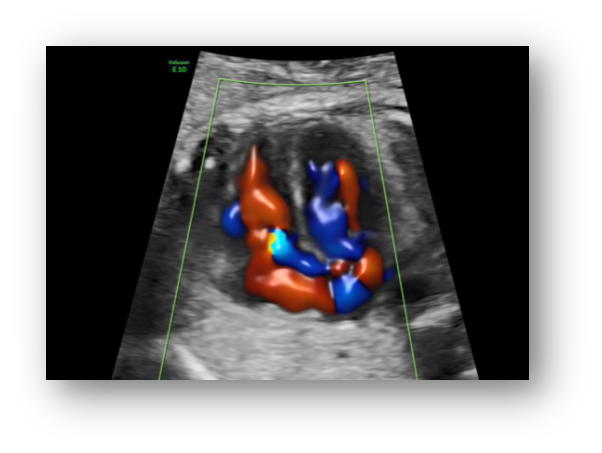

煊流成像技术可真实呈现胎心结构、脐带、血流变化,提升产前检查的诊断质量和效率。

6、胎儿心脏检测评估领域的技术领导者

孕中期胎儿心脏一直是产前筛查工作中的重难项目,所以胎心检查对于超声图像质量及辅助的诊断工具要求非常高。E10具备一整套领先的胎心成像技术,支持从胎儿心脏结构到心功能的全面分析,是胎儿心脏检测评估领域的技术领导。Voluson E10优异的图像分辨率,能更快地展现胎心结构和功能,双平面成像技术可实时观察胎心结构和血流变化,帮助临床医生及时作出准确诊断。